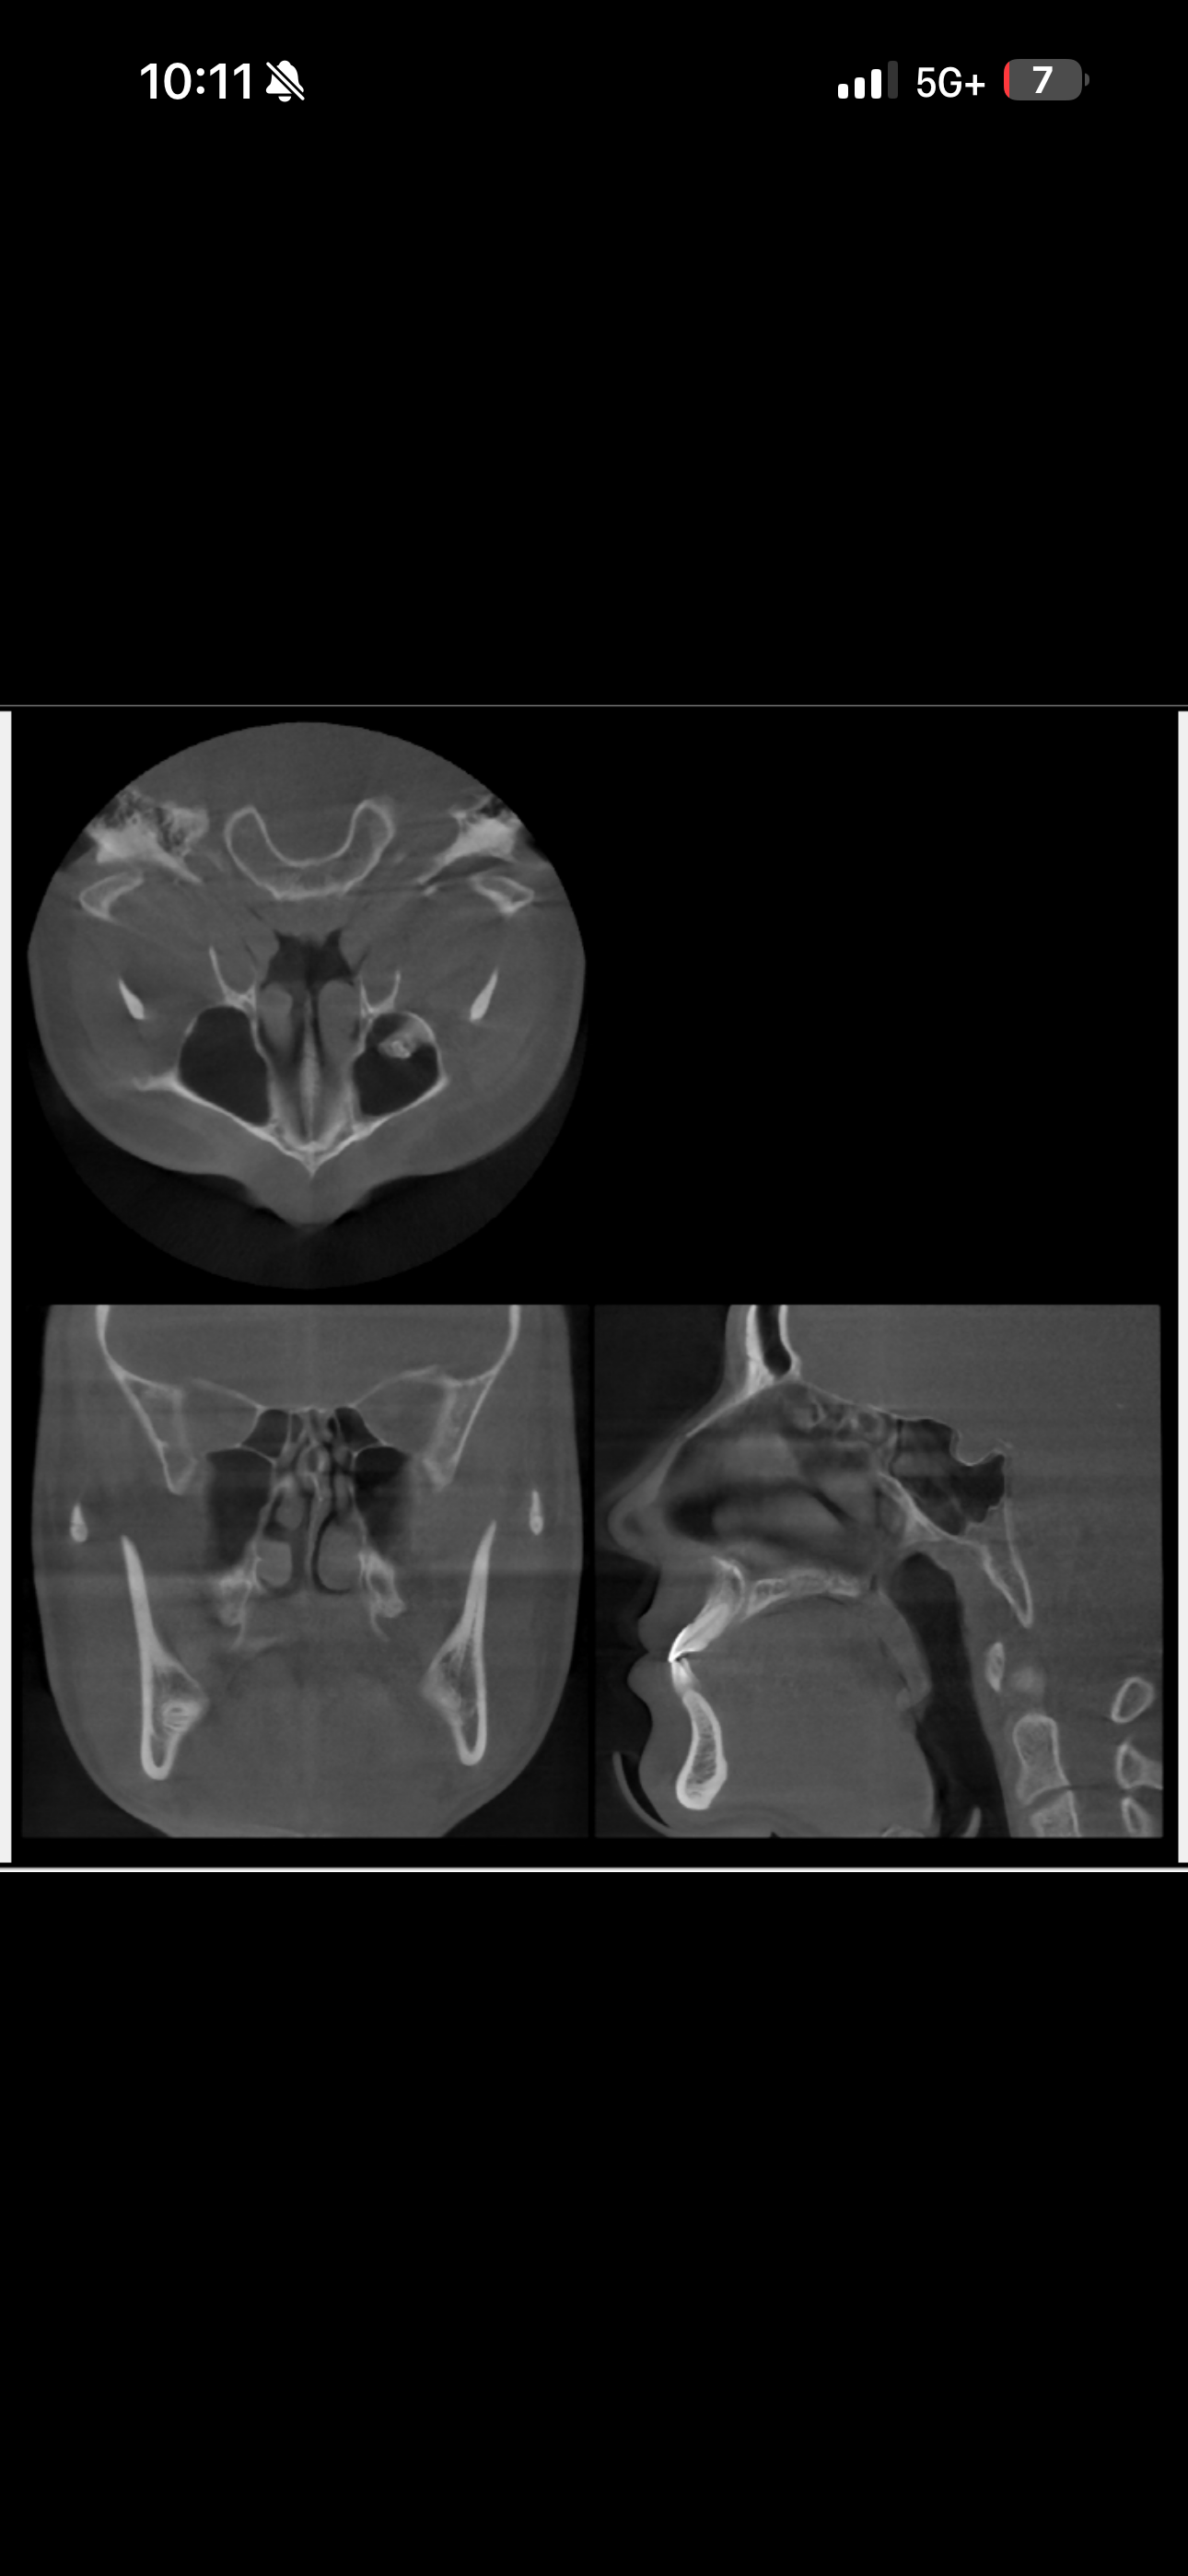

This is a CBT Scan I did a couple years back. Based on this results do I have proper tongue posture? I’m definitely looking into getting my septum deviation corrected.